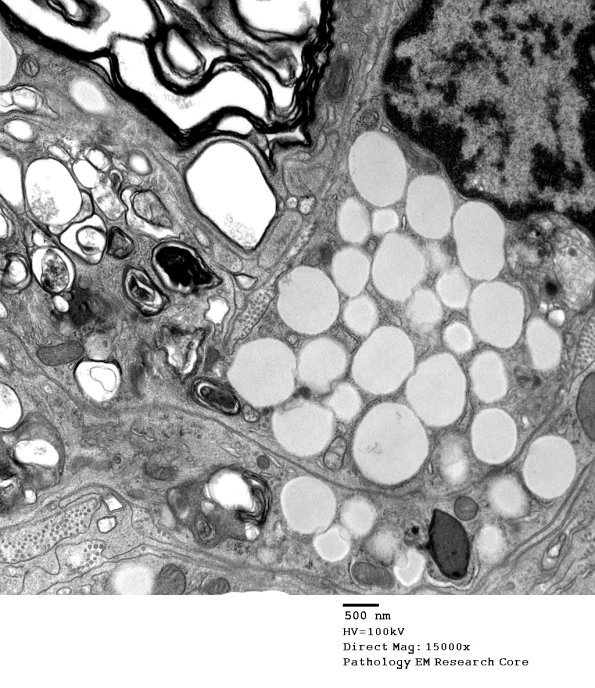

Washington University Experience | PERIPHERAL NEUROPATHY | 4 AXONAL DEGENERATION | 4 Macrophages | 3C4 Axonal Degeneration, macrophage phagocytosis (Case 8) EM 009 - Copy

An additional image of the macrophage contact with the degenerating Schwann cell contents.